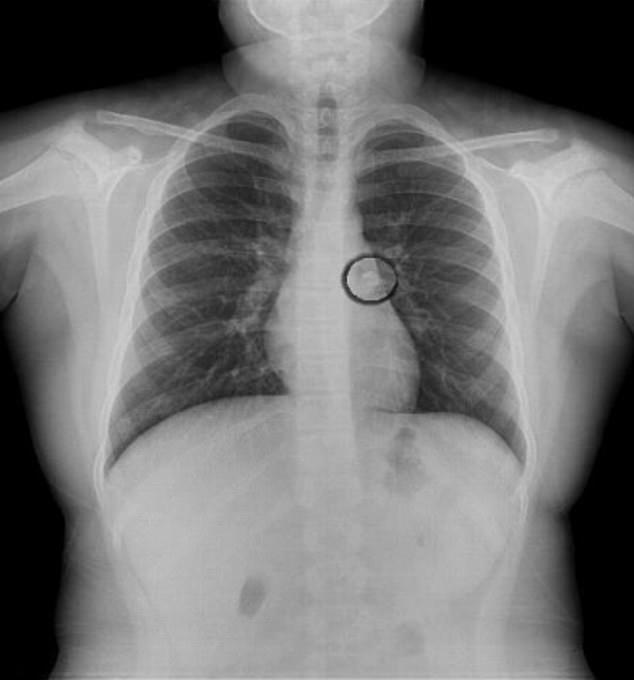

Sau khi tới viện và kiểm tra X-quang, phát hiện chiếc răng đã nằm trong đường dẫn khí đến phổi trái. Theo các bác sĩ, tỷ lệ tử vong khi một đứa trẻ hít phải vật lạ là khá cao nhưng cô bé này đã may mắn sống sót.

Chỉ tới khi được bác sĩ kiểm tra sơ bộ mới có thể nhận thấy phổi trái hoạt động không bình thường và tiến hành chụp X-quang ngực. Chiếc răng sau đó đã được lấy ra khỏi cơ thể bé gái.